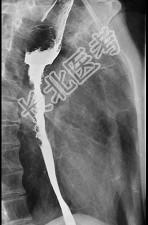

- 单项选择题女性患者,67岁进行性吞咽困难半年, X线及CT检查如图,应诊断为 ( )

A、食管癌

B、食管憩室

C、食管炎

D、食管良性狭窄

E、食管静脉曲张